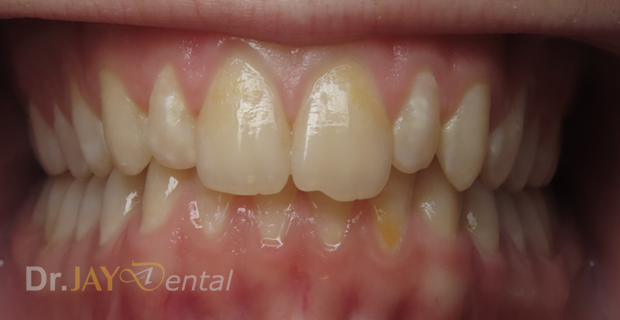

CASE 12

Patient has deep bite , crowding of teeth , narrow jaws , had airway issues. Deepbite corrected, upper and lower jaws expanded , increase in vertical height of the jaws . At our office, myofunctional therapy , using functional appliances created a harmonious balance for patient’s airway and oral structures

Before

After